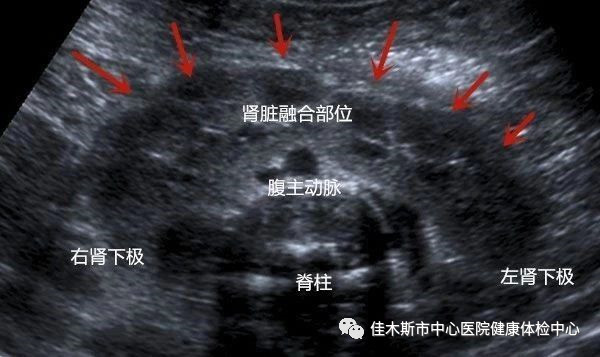

2019年4月23日,佳木斯市中心醫院健康體檢中心迎來一位體檢者,男性,59歲,既往從未進行過體檢,在子女陪同下前來進行全面檢查,主檢醫根據年齡、生活習慣和臨床表現為其推薦針對性的體檢項目,在進行腎臟彩超檢查時發現雙腎形態異常,上極實質于腹主動脈前相連,未見明顯占位性病變,體檢中心彩超會診組診斷為馬蹄腎,主檢醫對體檢者尿化驗、腎功、腫瘤系列等檢查進行綜合分析均未見明顯異常。馬蹄腎為先天發育異常,現階段并未出現腎炎等并發癥,暫不需特殊治療,建議定期復查腎臟。

馬蹄腎是指兩側腎的上極或下極在脊柱大血管前相互融合在一起,形成“馬蹄鐵”形的先天性腎臟發育畸形。多發生在胎兒早期(第4~7周),上極融合大多發生較遲,約在第9周,大部分為下極融合,只有少數為上極融合,兩腎融合的部位稱為峽部。

腎臟彩超、CT等影像學檢查顯示兩腎下極或上極相連,橫過下腔靜脈和腹主動脈前方。